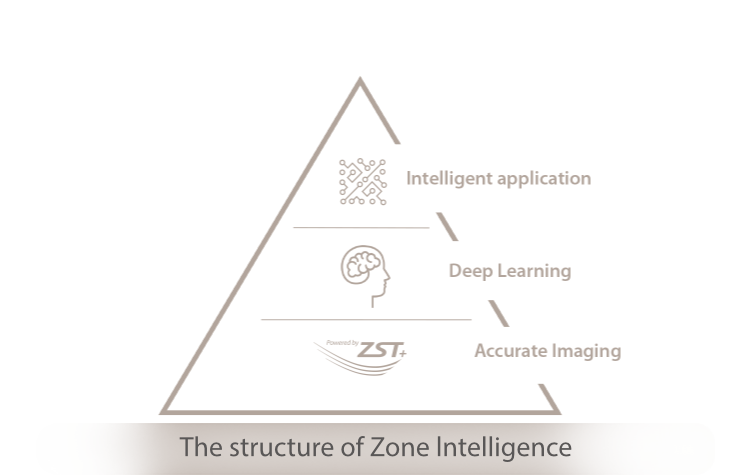

ReenvĂo inteligente a inteligencia clĂnica

Con tecnologĂa de la plataforma ZST + basada sobre canal de datos, el Nuewa R9 con Zone Intelligence 2.0 crea un mecanismo realmente inteligente para ofrecer un nuevo nivel de inteligencia.

Inteligencia artificial basada

en el conocimiento del dominio

De frontend a backend

OptimizaciĂłn de imĂĄgenes